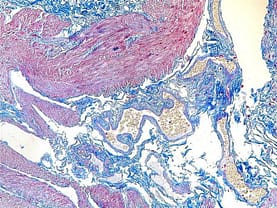

Massons trichrome

Masson’s trichrome stain combines the use of three dyes to selectively stain different tissue components. The technique involves staining nuclei and muscle fibers with Weigert’s iron hematoxylin, cytoplasm with Biebrich scarlet-acid fuchsin, and collagen fibers with aniline blue or light green. The staining process results in distinct colors for different tissue structures.

The nuclei appear dark blue or black, muscle fibers appear red, and collagen fibers are stained green or blue. This stain provides a sharp contrast between these components, enabling the identification and evaluation of tissues with collagenous structures, such as connective tissue, fibrotic tissue, and scar tissue.

Black-Nuclei

Red-Cytoplasm, muscle, erythrocytes

Collagen- blue

Application of Masson’s trichrome stain commonly used in the assessment of diseases involving fibrosis, such as liver fibrosis, myocardial fibrosis, and pulmonary fibrosis. It helps to visualize and quantify collagen deposition and fibrotic changes in tissues, aiding in the diagnosis and evaluation of various pathological conditions.